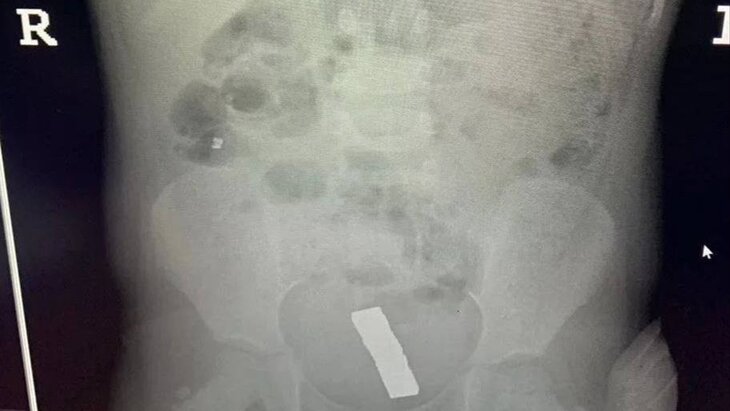

Врачи в подмосковной Балашихе спасли девочку, которая проглотила 20 магнитных шариков. Об этом сообщает телеканал "360" со ссылкой на Минздрав Московской области.

Ребенок поступил в медучреждение с болями в животе. Магниты были обнаружены в кишечнике после обследования.

Юную пациентку направили в детское хирургическое отделение и извлекли шарики в ходе лапароскопической операции через проколы. Для этого медики использовали эндоскоп и специальный инструмент, рассказал заведующий отделением детской хирургии Балашихинской больницы Эмир Жамынчиев.

По его словам, из-за большой силы притяжения магниты образовали в кишке отверстие, которое врачи ушили после их извлечения. Он добавил, что 5 шариков успели переместиться в малый таз.